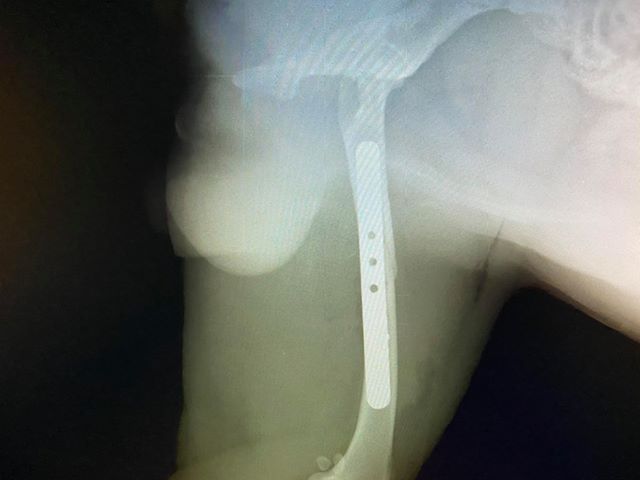

Όπως έγινε γνωστό, ο Ρόκι υπέστη κάταγμα του μηριαίου και έπρεπε να υποβληθεί σε χειρουργική επέμβαση για να μπορεί να σταθεί και πάλι στα πόδια του.

Για το συμβάν ενημερώθηκε η Φιλοζωική Ομάδα Βόλου. Ο άτυχος σκύλος υποβλήθηκε σε τρίωρη χειρουργική επέμβαση η οποία ήταν επιτυχής και σήμερα αναρρώνει.